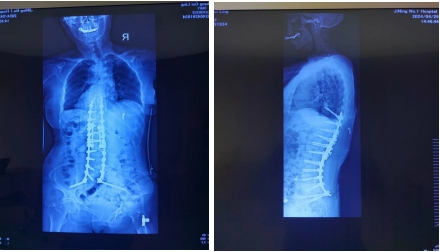

术后脊柱全长正侧位片:

术前评估矢状面及冠状面,SVA:22cm、CBD:2cm、冠状面Cobb角:14°、TPA:65°、GK:65°、TLK:42°、LL:-16°、PI:55°、SS:10°、PT:45°。经过多学科会诊及科室内讨论,对潜在风险、替代治疗方案系统评估后,患者接受了胸8至骶骨的后路长节段融合手术,后路多节段Ponte截骨。手术采用3D打印导板和导航协助置钉,超声骨刀截骨,电生理监护神经功能,手术顺利,矫形满意。实施本次手术时,我们使用了三项新技术,第一项新技术是经骶2骶髂螺钉(S2AI)固定,固定坚强,恢复矢状面平衡,预防远端交界性后凸。第二项新技术是卫星棒的使用,用多棒和序贯的理念矫形,降低术后断棒的风险。第三项新技术是斜向钉的使用,螺钉向头侧穿过3层皮质,减少对近端软组织的损伤,预防近端交界性后凸。术后镇痛、理疗、药物DVT预防,早期康复锻炼。术后第4天拔除引流管后下地活动,术后第7天康复出院。患者下地活动后,腰部疼痛较术前明显好转,双下肢肌力提高至4+级,神经源性跛行得到缓解,部分恢复生活自理能力。术后评估矢状面及冠状面,SVA:3cm、CBD:2cm、冠状面Cobb角:8°、TPA:24°、GK:14°、TLK:9°、LL:43°、PI:53°、SS:19°、PT:34°。